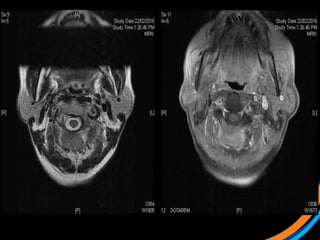

Case study 2(Patient 003) • 37 F, ECOG 0 • Met cervical Ca • On PDL1 clinical trial • Symptomatic L1 met s/p stabilisation • For post-op SBRT  1) Review the images  2) Target the lesion *Post-op targeting is more subjective. Post-op consensus guidelines likely to be out in Red Journal soon

• #31 Sag T1, Sag T1c

• #32 Ax T2 Ax T1C

• #33 Sag STIR

• #37 Post-instrumentation diagnostic CT